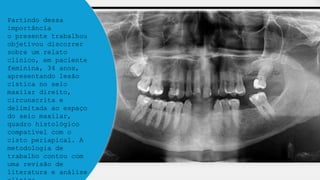

Partindo dessa

importância

o presente trabalhou

objetivou discorrer

sobre um relato

clínico, em paciente

feminina, 34 anos,

apresentando lesão

cística no seio

maxilar direito,

circunscrita e

delimitada ao espaço

do seio maxilar,

quadro histológico

compatível com o

cisto periapical. A

metodologia de

trabalho contou com

uma revisão de

literatura e análise

Partindo dessa importância o presentetrabalhou objetivou discorrer sobre um relato clínico, em paciente feminina, 34 anos, apresentando lesão cística no seio maxilar direito, circunscrita e delimitada ao espaço do seio maxilar, quadro histológico compatível com o cisto periapical. A metodologia de trabalho contou com uma revisão de literatura e análise